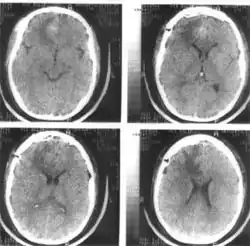

Компьютерная томография (КТ) и магнитно-резонансная томография (МРТ) — наиболее важные диагностические исследования при инсульте. КТ в большинстве случаев позволяет чётко отдифференцировать «свежее» кровоизлияние в мозг от других типов инсультов, МРТ предпочтительнее для выявления участков ишемии, оценки распространённости ишемического повреждения и пенумбры. Также с помощью этих исследований можно выявлять первичные и метастатические опухоли, абсцессы мозга и субдуральные гематомы. Если наблюдается ригидность затылочных мышц, но отсутствует отёк диска зрительного нерва, люмбальная пункция в большинстве случаев позволит быстро установить диагноз кровоизлияния в мозг, хотя при этом сохраняется незначительный риск возникновения синдрома «вклинения» мозга. В случаях, когда есть подозрения на эмболию, люмбальная пункция необходима, если предполагается применение антикоагулянтов. Люмбальная пункция имеет также важное значение для диагностики рассеянного склероза и, кроме того, может иметь диагностическое значение при нейроваскулярном сифилисе и абсцессе мозга[39]. При недоступности КТ или МРТ необходимо выполнить эхоэнцефалографию и люмбальную пункцию.